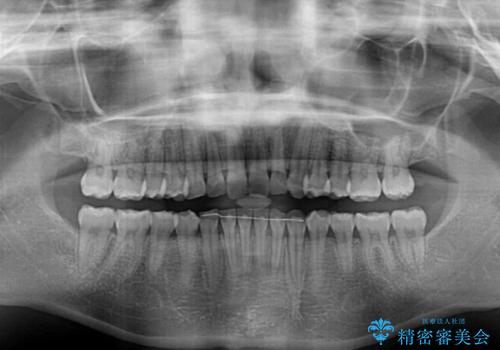

咬合力の緩和と食いしばりがちな咬み合わせが改善され、顎の負担が大幅に軽減されました。

当初は睡眠時のマウスピースのみの製作をご希望でしたが、矯正治療の提案をしたところ、インビザラインにて矯正治療を行うこととなりました。

矯正治療中に食いしばりがより強くなることがあるため、半年に1回のペースでボツリヌストキシンによる咬合力緩和を並行して行うこととしました。